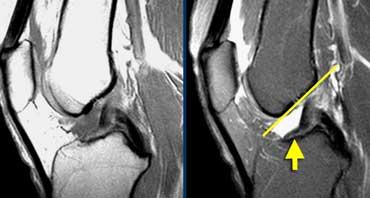

Hình bên trái là một vận động viên đi bộ tốc độ cao với triệu chứng đau mặt ngoài gối.

Bình thường phải có mô mỡ giữa dải chậu chày và lồi cầu ngoài, nhưng trong trường hợp này mô mỡ không còn hiện diện.

Hội chứng ma sát dải chậu chày: Dịch trong túi hoạt dịch thấy được giữa dải chậu chày và xương đùi (mũi tên vàng). Dịch khớp dừng lại tại các mũi tên đỏ.

Cùng bệnh nhân trên. Trên các lát cắt axial, có thể thấy dịch trong túi hoạt dịch nằm giữa dải chậu chày và xương đùi bên dưới.

Đôi khi cần phân biệt dịch tại vị trí này với dịch khớp.

Cần xem xét toàn bộ các lát cắt hình ảnh.

Trong trường hợp này, dịch khớp dừng lại tại các mũi tên đỏ.